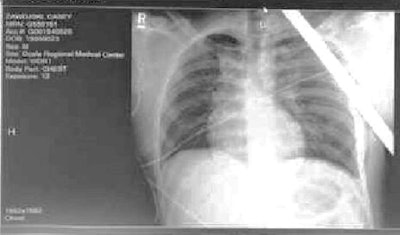

Doctors tell the paper that the rebar somehow missed all of Zawojski’s vital organs, though it did collapse one of his lungs and damaged several ribs. The rebar came to rest just below his collar bone and two main blood vessels. He is expected to make a full recovery.